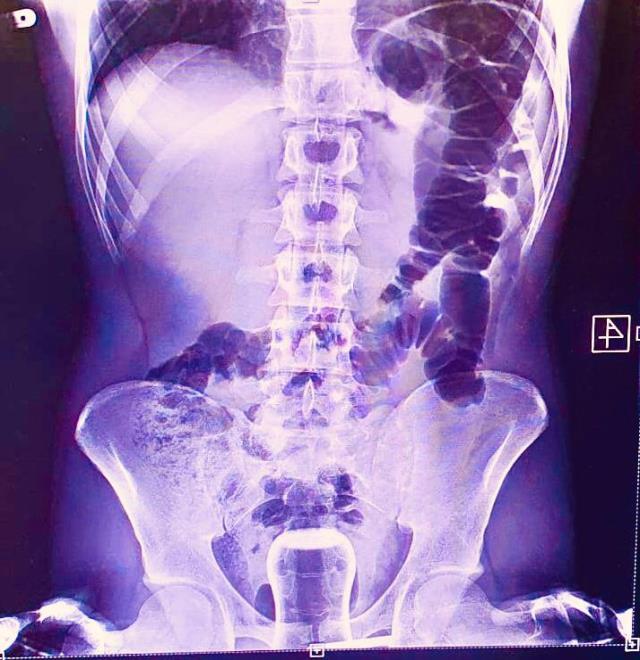

Hacamat faciayla bitti! Çay bardağı ameliyat ile çıkarıldı! Şanlıurfa’da basur hastası olan bir vatandaş, uzun süreden bu yana acısını çektiği hastalık nedeniyle hacamat yaptırmaya karar verdi. Öğrenilen bilgilere göre hacamat sırasında yağlı bardak, şahsın anüs bölgesine kaçtı. Vatandaş durumu bir hafta sonra fark etti.

Şanlıurfa’da akıl almaz bir olay meydana geldi. Uzun süreden bu yana basur hastalığı çeken bir vatandaş, acılarının artmasının ardından geleneksel tedavi yöntemleri arasında bulunan hacamat yöntemini seçti. Hacamat yaptırdığı esnada yağlı çay bardağı anüs bölgesine kaçtı. Bardak ameliyatla çıkarıldı.